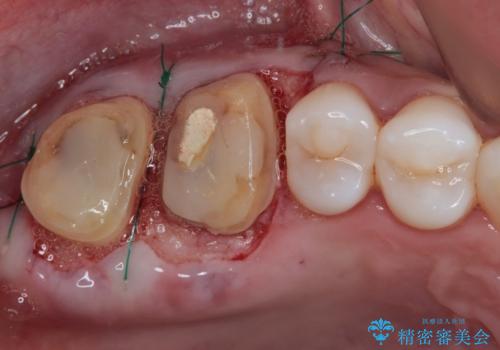

隣接する部分の間のむし歯が歯肉の奥深くにまで及んでおり、歯肉が腫れやすい状態となっていたため、歯肉の切除並びに歯槽骨の形態修正を行い、虫歯が歯肉の外に出てくるようにした上で、オールセラミックにて補綴することとしました。